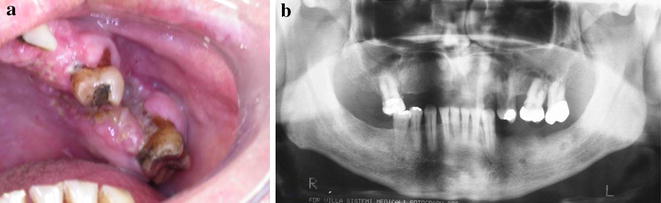

A 63-year-old male complaining about a “wound in the mouth” was referred to Goiás Oral Medicine Center, Federal University of Goiás Dental School, Goiânia, Brasil, for diagnosis and treatment. The patient reported that the lesion had approximately 6 months of evolution and that he was asymptomatic and had not experienced any bleeding. His medical and dental history did not show any significance or any relation to his lesion. The patient had been a smoker for 33 years. Intraoral examination revealed a destructive ulcerative lesion around the upper left first and second molars, which showed mobility and poor dental conditions, including dental caries, gingival recession and bone loss (Fig. 1a). A panoramic radiograph revealed a radiolucent area in the periapical region of the upper left first molar, suggesting an osteolytic lesion (Fig. 1b). According to the clinical and radiographic features, the main diagnostic hypotheses were periodontal disease associated with oral squamous cell carcinoma. The patient reported that there was no cancer in his family history. The results of laboratory analyses, including blood and urine studies, were within the normal range. We also performed a biopsy to provide histopathological analysis. At this time, the patient took prescribed antibiotics for 7 days and underwent surgery of the upper left primary molar. Microscopic findings showed an inflammatory infiltrate rich in plasma cells that is commonly present in periodontal disease, without the presence of any atypical cell in this specimen of oral mucosa. Based on these findings, periodontal disease was considered as the diagnosis and the patient underwent periodontal therapy twice without remission of the initial injury. During follow-up, it was observed that the lesion increased considerably.

Fig. 1.

Intraoral (a) and panoramic radiograph (b) showed a lesion around the upper left first and second molars